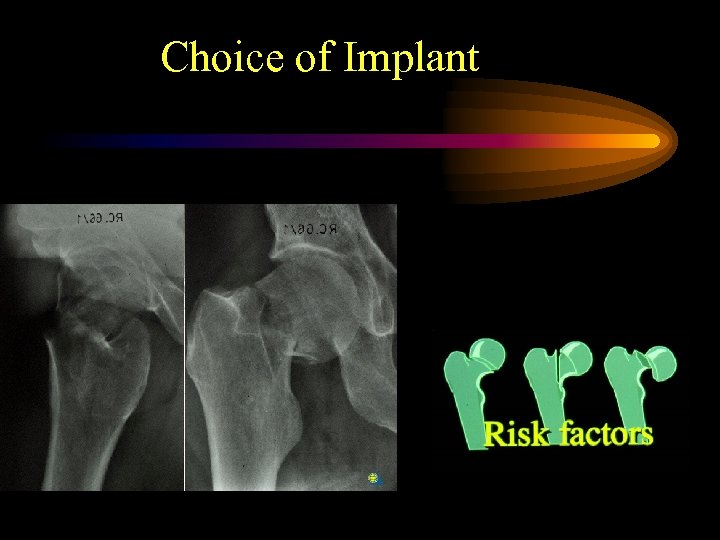

Fracture related pattern of femoral neck fractures representing risk for osteofixation failure, non-union and avascular necrosis • Grade of dislocation (Garden 1972, Thorngren 1991) • Size of head fragment (Benterud et al. Acta Orth Scand 1994) • Posterior comminution (Benterud et al. 1997) • Osteoporosis (Bentley 1972, Riska 1969, Anderson 1969, Thorngren 1995)

Fracture related pattern of femoral neck fractures representing risk for osteofixation failure, non-union and avascular necrosis • Grade of dislocation (Garden 1972, Thorngren 1991) • Size of head fragment (Benterud et al. Acta Orth Scand 1994) • Posterior comminution (Benterud et al. 1997) • Osteoporosis (Bentley 1972, Riska 1969, Anderson 1969, Thorngren 1995)

Choice of Implant

Choice of Implant